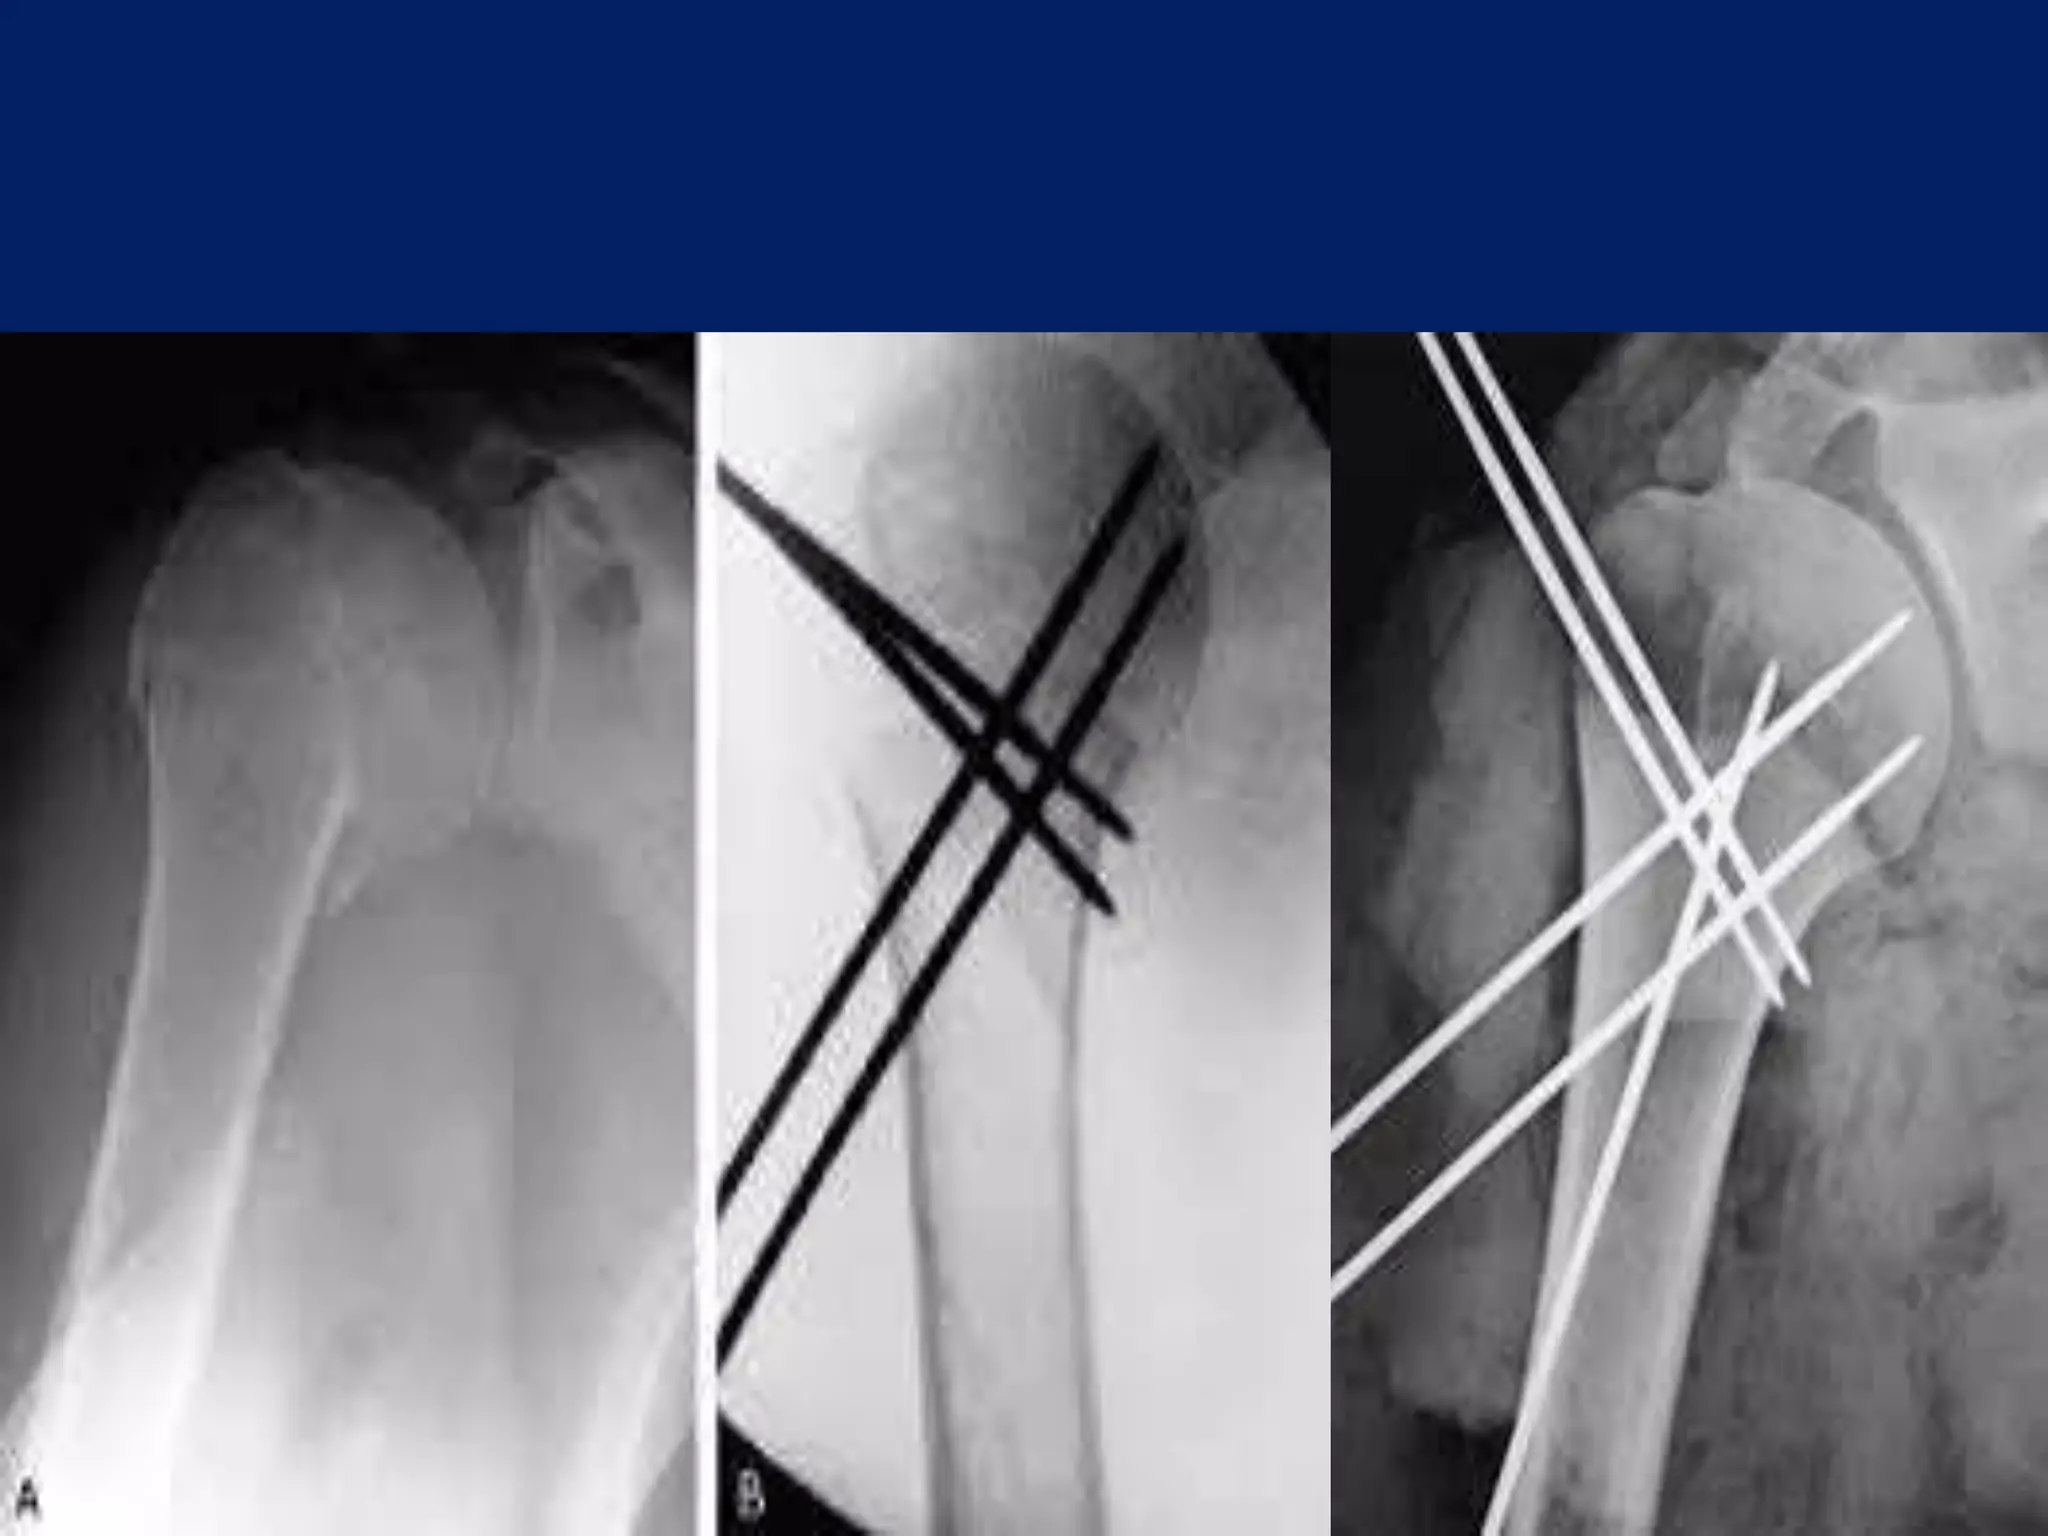

Fracture proximal humerus Fixation with K wires and External fixator

Operative contd... • 2.5mmSchanz pins/ K wire at humeral head at 300 to each other in horizontal plane. • 1st: In true lateral/ coronal plane 2nd: just lateral to bicipital groove 3rd: 300 posterior to 1st one.

• Next 2.5mmpin inserted in coronal plane in line with 1st pin, approximately 4cm or 3 finger/ below the 1st pin in upper third of Humerus. • 3rd pin placed 2cm below the above pin laterally. • Wires are placed from lateral cortex to medial cortex into the head upto the subchondral area